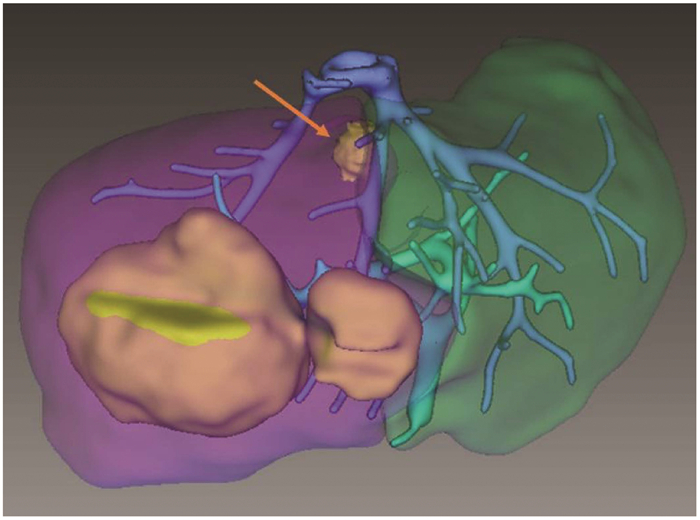

Effectiveness and safety of ultrasound-guided ablation in treatment of primary liver cancer in dangerous areas

Ting WANG, Chunyan WANG, Jianyong LIU, Yonghe ZHOU, Wei LU, Jia LI, Li ZHOU

2021, 37(7): 1594-1598. DOI: 10.3969/j.issn.1001-5256.2021.07.023

Abstract(973) HTML (267) PDF (2312KB)(86)

Abstract:

Objective  To investigate the effectiveness and safety of ultrasound-guided percutaneous local ablation in the treatment of liver cancer in dangerous areas.  Methods  A total of 179 patients with primary liver cancer who were admitted to Tianjin Second People's Hospital from January 2014 to September 2017 and underwent ultrasound-guided ablation for the first time were enrolled, and according to tumor location, the patients were divided into dangerous area group with 134 patients and non-dangerous area group with 45 patients. All patients received ablation therapy. The patients were followed up to observe tumor recurrence and death, and the patients without recurrence or death were followed up to September 2019. The two groups were compared in terms of complications after ablation, complete tumor response rate, tumor recurrence or progression, and postoperative survival. The two-independent-samples t-test was used for comparison of normally distributed continuous data between two groups; The Mann-Whitney U test was used for comparison of non- normally distributed continuous data between two groups, and the chi-square test was used for comparison of categorical data between two groups; the Kaplan-Meier method was used to analyze local tumor progression rate and cumulative survival rate, and the log-rank test was used for comparison between two groups.  Results  There were no significant differences in baseline levels between the two groups. There were no significant differences between the dangerous area group and the non-dangerous area group in the incidence rates of mild complications (42.5% vs 51.1%, χ2=1.002, P=0.317) and severe complications (6.0% vs 2.22%, χ2=0.453, P=0.290) and the reduction rate and normalization rate of alpha-fetoprotein within 1 month after ablation (reduction rate: 75.0% vs 80.0%, χ2=0.464, P=0.496; normalization rate: 33.9% vs 26.3%, χ2=0.381, P=0.537), and there was also no significant difference in complete tumor response rate between the two groups (91.8% vs 93.3%, P=0.990). The dangerous area group had 1- and 2-year progression-free survival rates of 60.7% and 37.1%, respectively, and the non-dangerous area group had 1- and 2-year progression-free survival rates of 63.5% and 55.0%, respectively, with a median progression-free survival time of 18 months and 27 months, respectively, and there was no significant difference between the two groups (χ2=0.573, P=0.449). The dangerous area group had 1- and 2-year cumulative survival rates of 96.8% and 90.3%, respectively, and the non-dangerous area group had 1- and 2-year cumulative survival rates of 93.3% and 87.8%, respectively, with no significant difference between the two groups (χ2=0.110, P=0.731).  Conclusion  Ultrasound-guided percutaneous local ablation is a feasible, safe, and effective method for the treatment of liver cancer in dangerous areas.